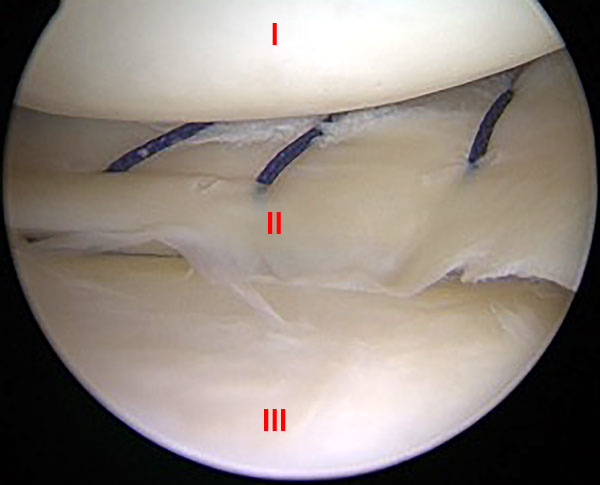

En un primer tiempo se realizó la reparación del cuerno posterior del menisco interno. Para obtener un acceso con mejor visión y mas seguro realizamos la técnica de pie-crust sobre el LCM. Se preparan con shaver los bordes de la lesión, para mejorar el potencial de cicatrización.29 Luego se realiza la sutura meniscal fuera-adentro, con 3 puntos verticales ubicados cada 3 a 5 mm, utilizando aguja espinal de (18 gauge) precargada con sutura no absorbible, polidioxanona número 1 (PDS) a través de un portal postero medial estándar que se creó bajo la visualización artroscópica directa de la cápsula posteromedial. Logrando de esta forma la reducción anatómica y compresión circunferencial del menisco (fig. 4).

Figura 4: Imagen artroscópica de rodilla derecha, vista desde el portal anteromedial que muestra que muestra la sutura meniscal fuera- adentro con 3 puntos verticales de sutura no absorbible, polidioxanona N° 1 (PDS). I: Cóndilo Femoral Interno. II: Puntos Verticales con PDS en Curno Post. Menisco Int. III: Meseta Tibial Interna.